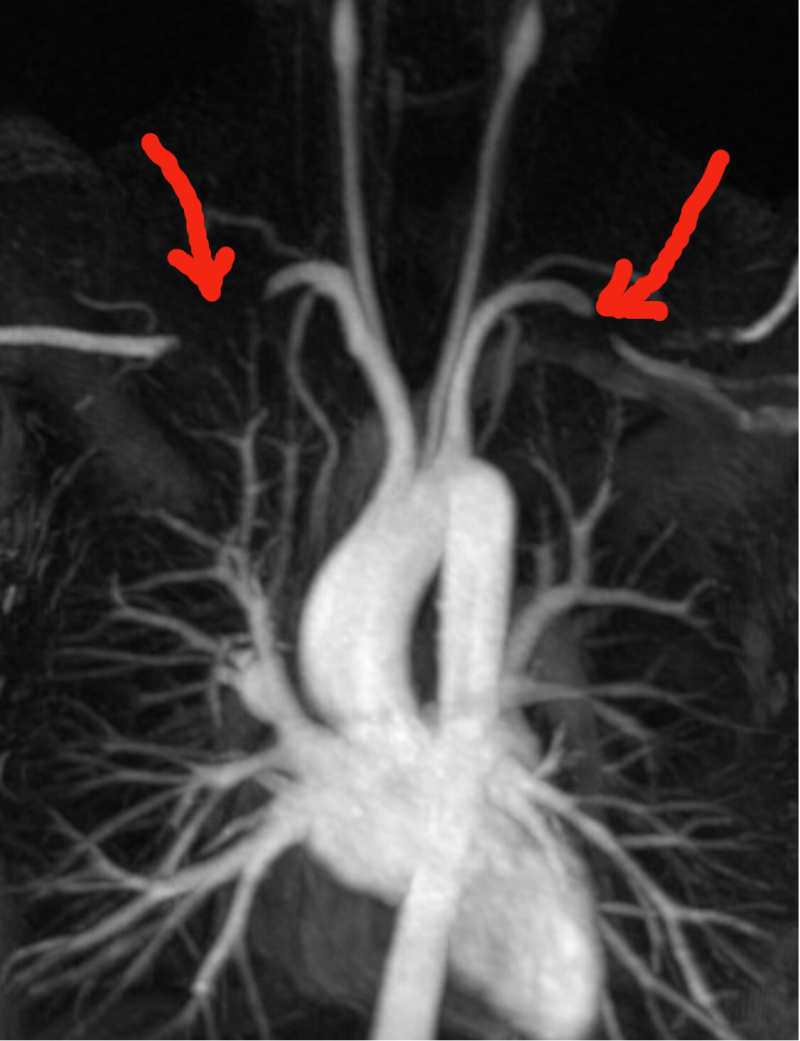

Anhand eines Angio MRT lassen sich in Provokationsstellung mit erhobenen Armen (rote Pfeile) in einigen Fällen Gefässbeeinträchtigungen nachweisen bei in Ruhe normalen Flussbedingungen. Flussunregelmässigkeiten lassen sich auch teilweise von angiologischer Seite mittels Ultraschall nachweisen.